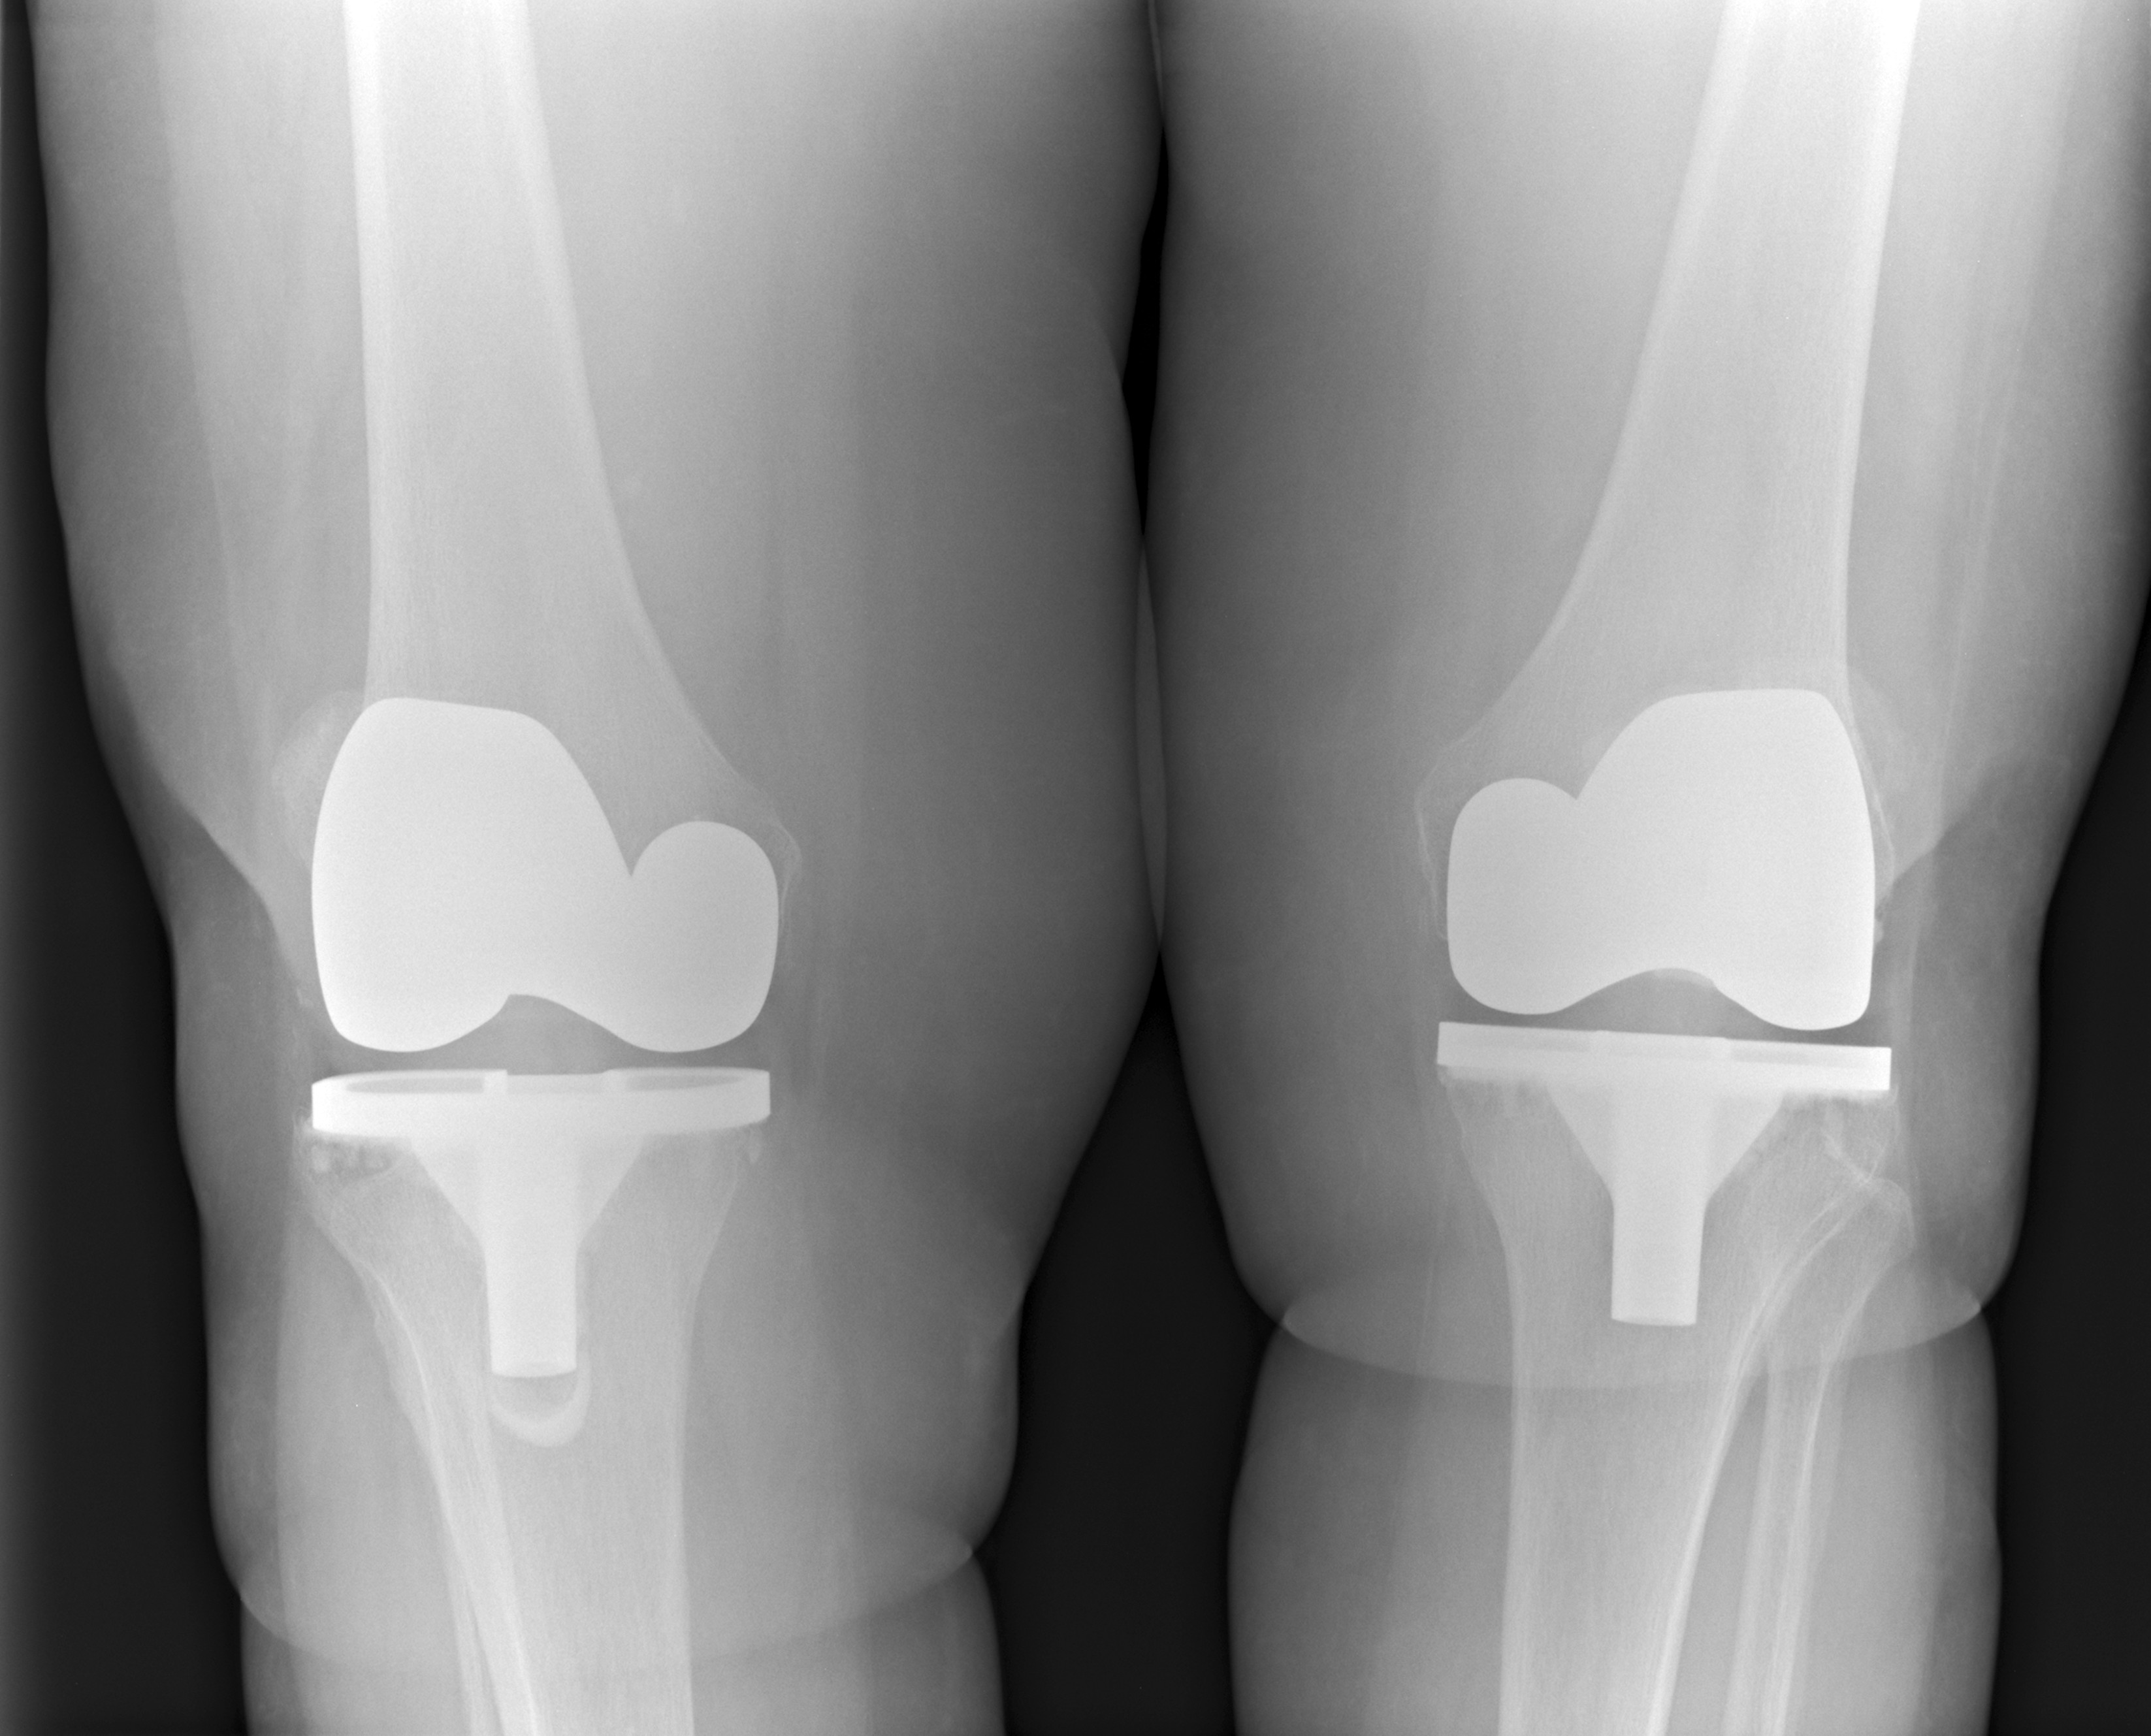

무릎인공관절 수술은 걷기 불편함과 통증으로 일상생활이 어려운 분들에게 중요한 치료 방법입니다. 특히 65세 이상 여성 환자들에게서 시행 비율이 높으며, 무릎 통증이 심하거나 관절 운동이 제한되는 경우 좋은 해결책이 될 수 있습니다. 하지만 수술 자체보다 더 중요한 건 그 이후의 회복 과정입니다. 아무리 수술이 잘 됐더라도 재활이 제대로 이뤄지지 않으면 기대한 만큼의 효과를 보기 어렵습니다. 이 글에서는 수술 후 꼭 알아야 할 운동법, 통증 관리 방법, 그리고 보조기 사용까지 실제 회복에 도움이 되는 내용을 정리했습니다.